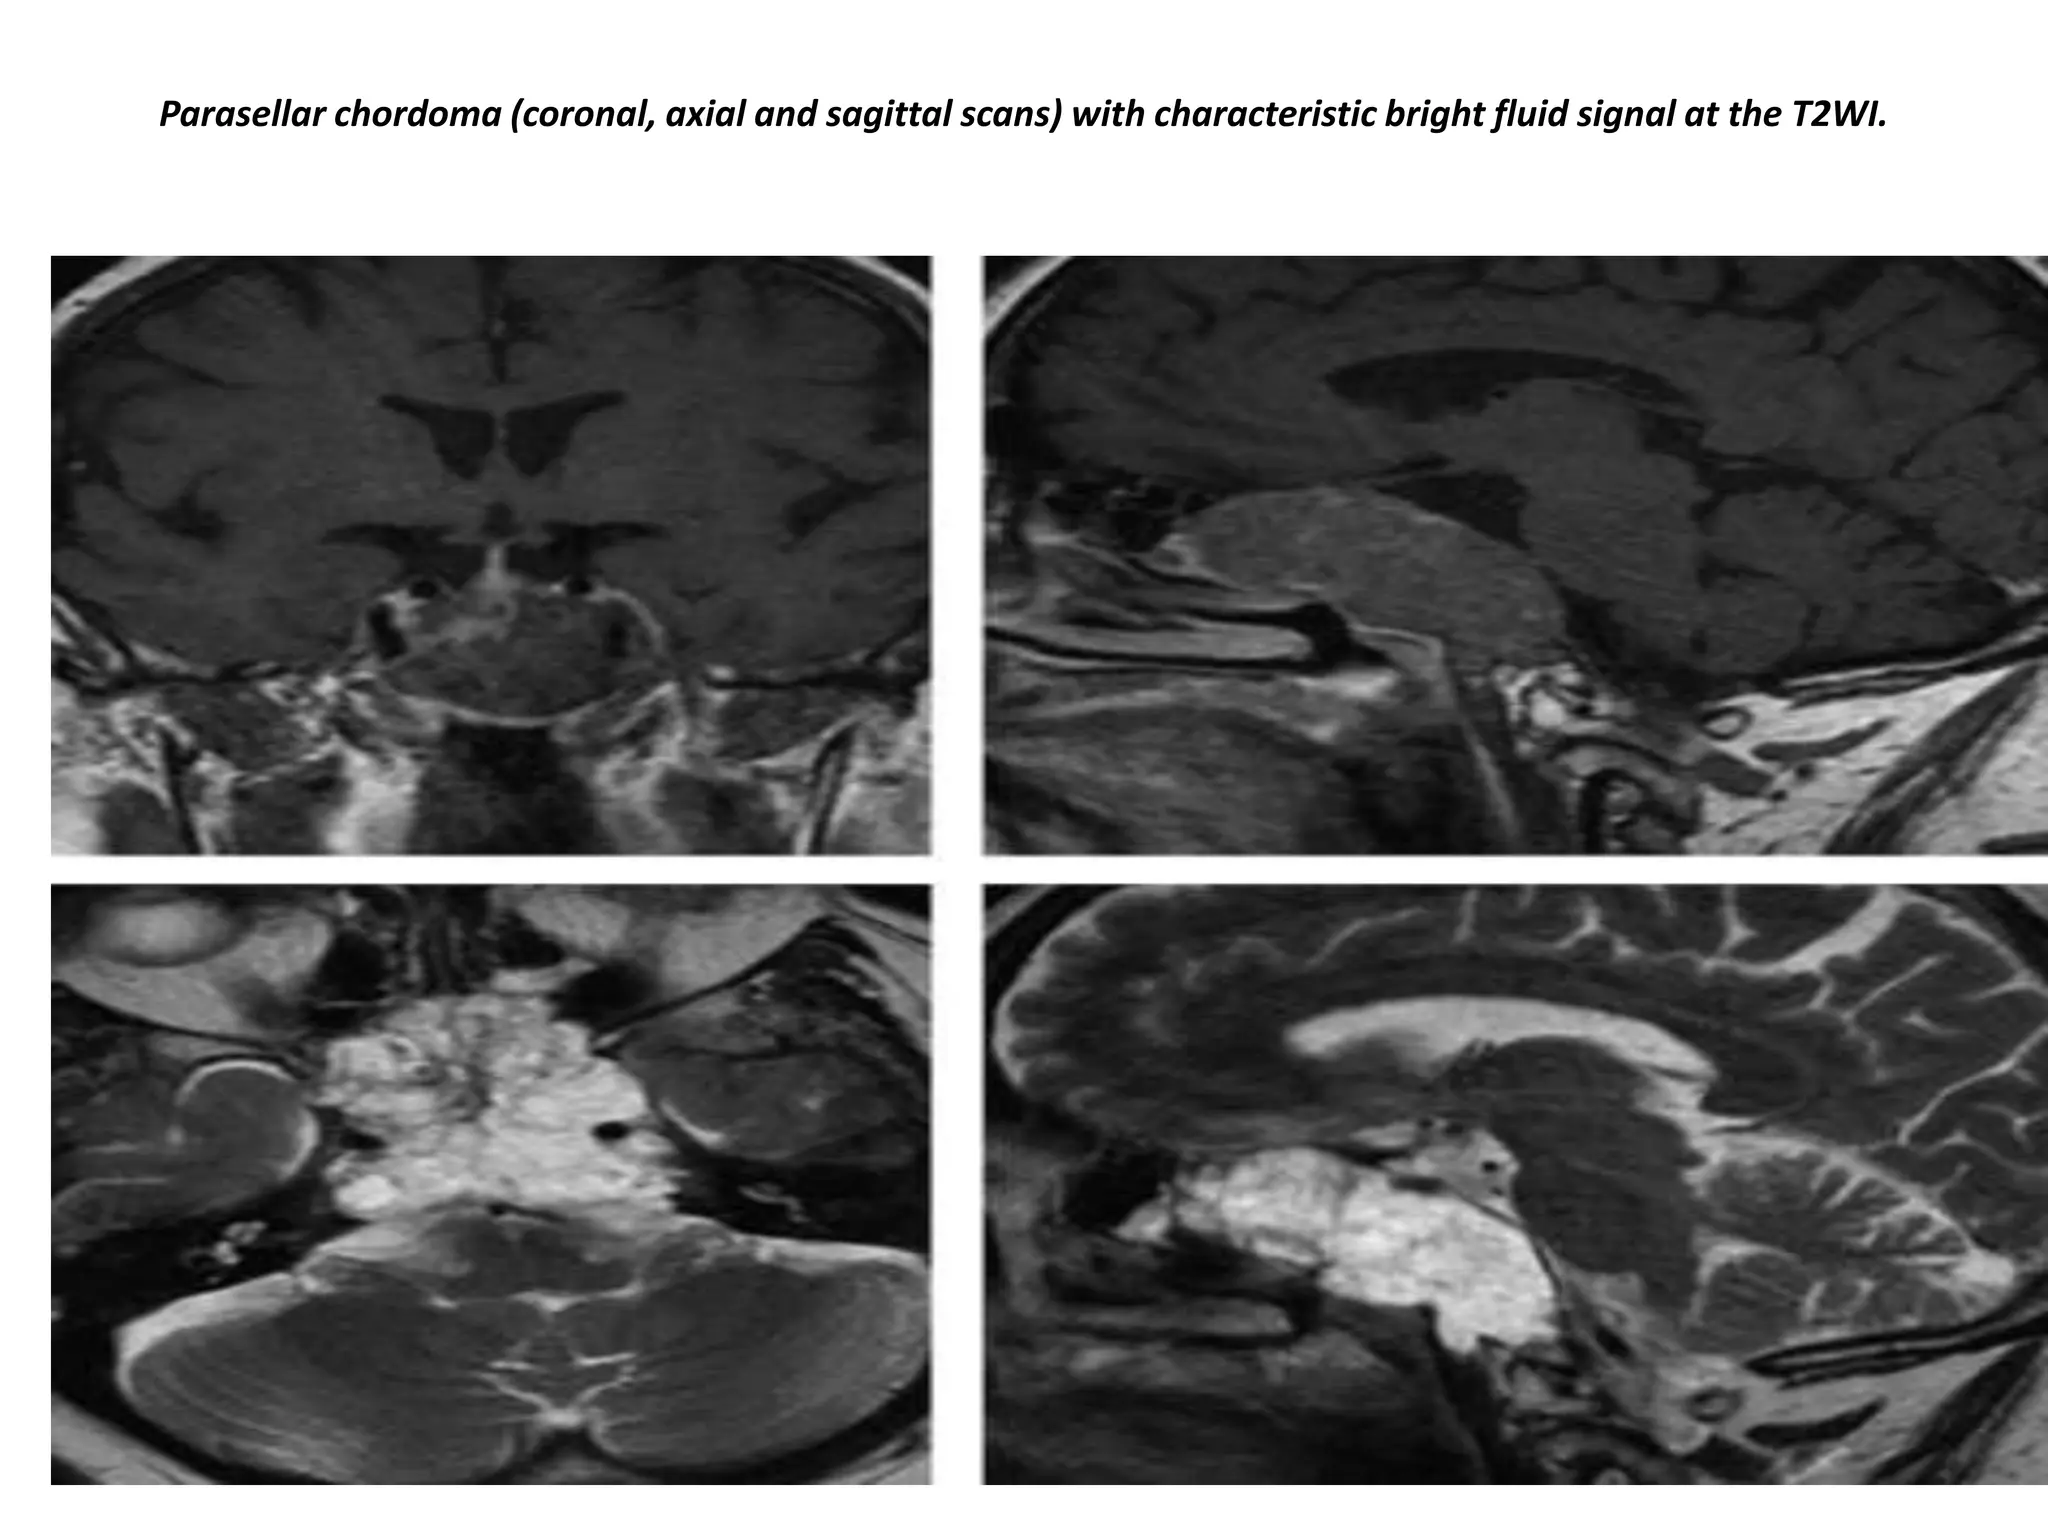

Parasellar chordoma (coronal, axial and sagittal scans) with characteristic bright fluid signal at the T2WI.

Chordomas are the most common lesions of the clivus, also a favored location for metastases and chondrosarcomas. his

patient has a normal pituitary gland. Posterior to this is a large, fungating mass positioned at the level of the clivus. The CT

shows some calcifications in this area. The differential diagnosis for this mass would be chondroma or chondrosarcoma.

Chordomas tend to occur in the midline, whereas condrosarcomas tend to occur off the midline.